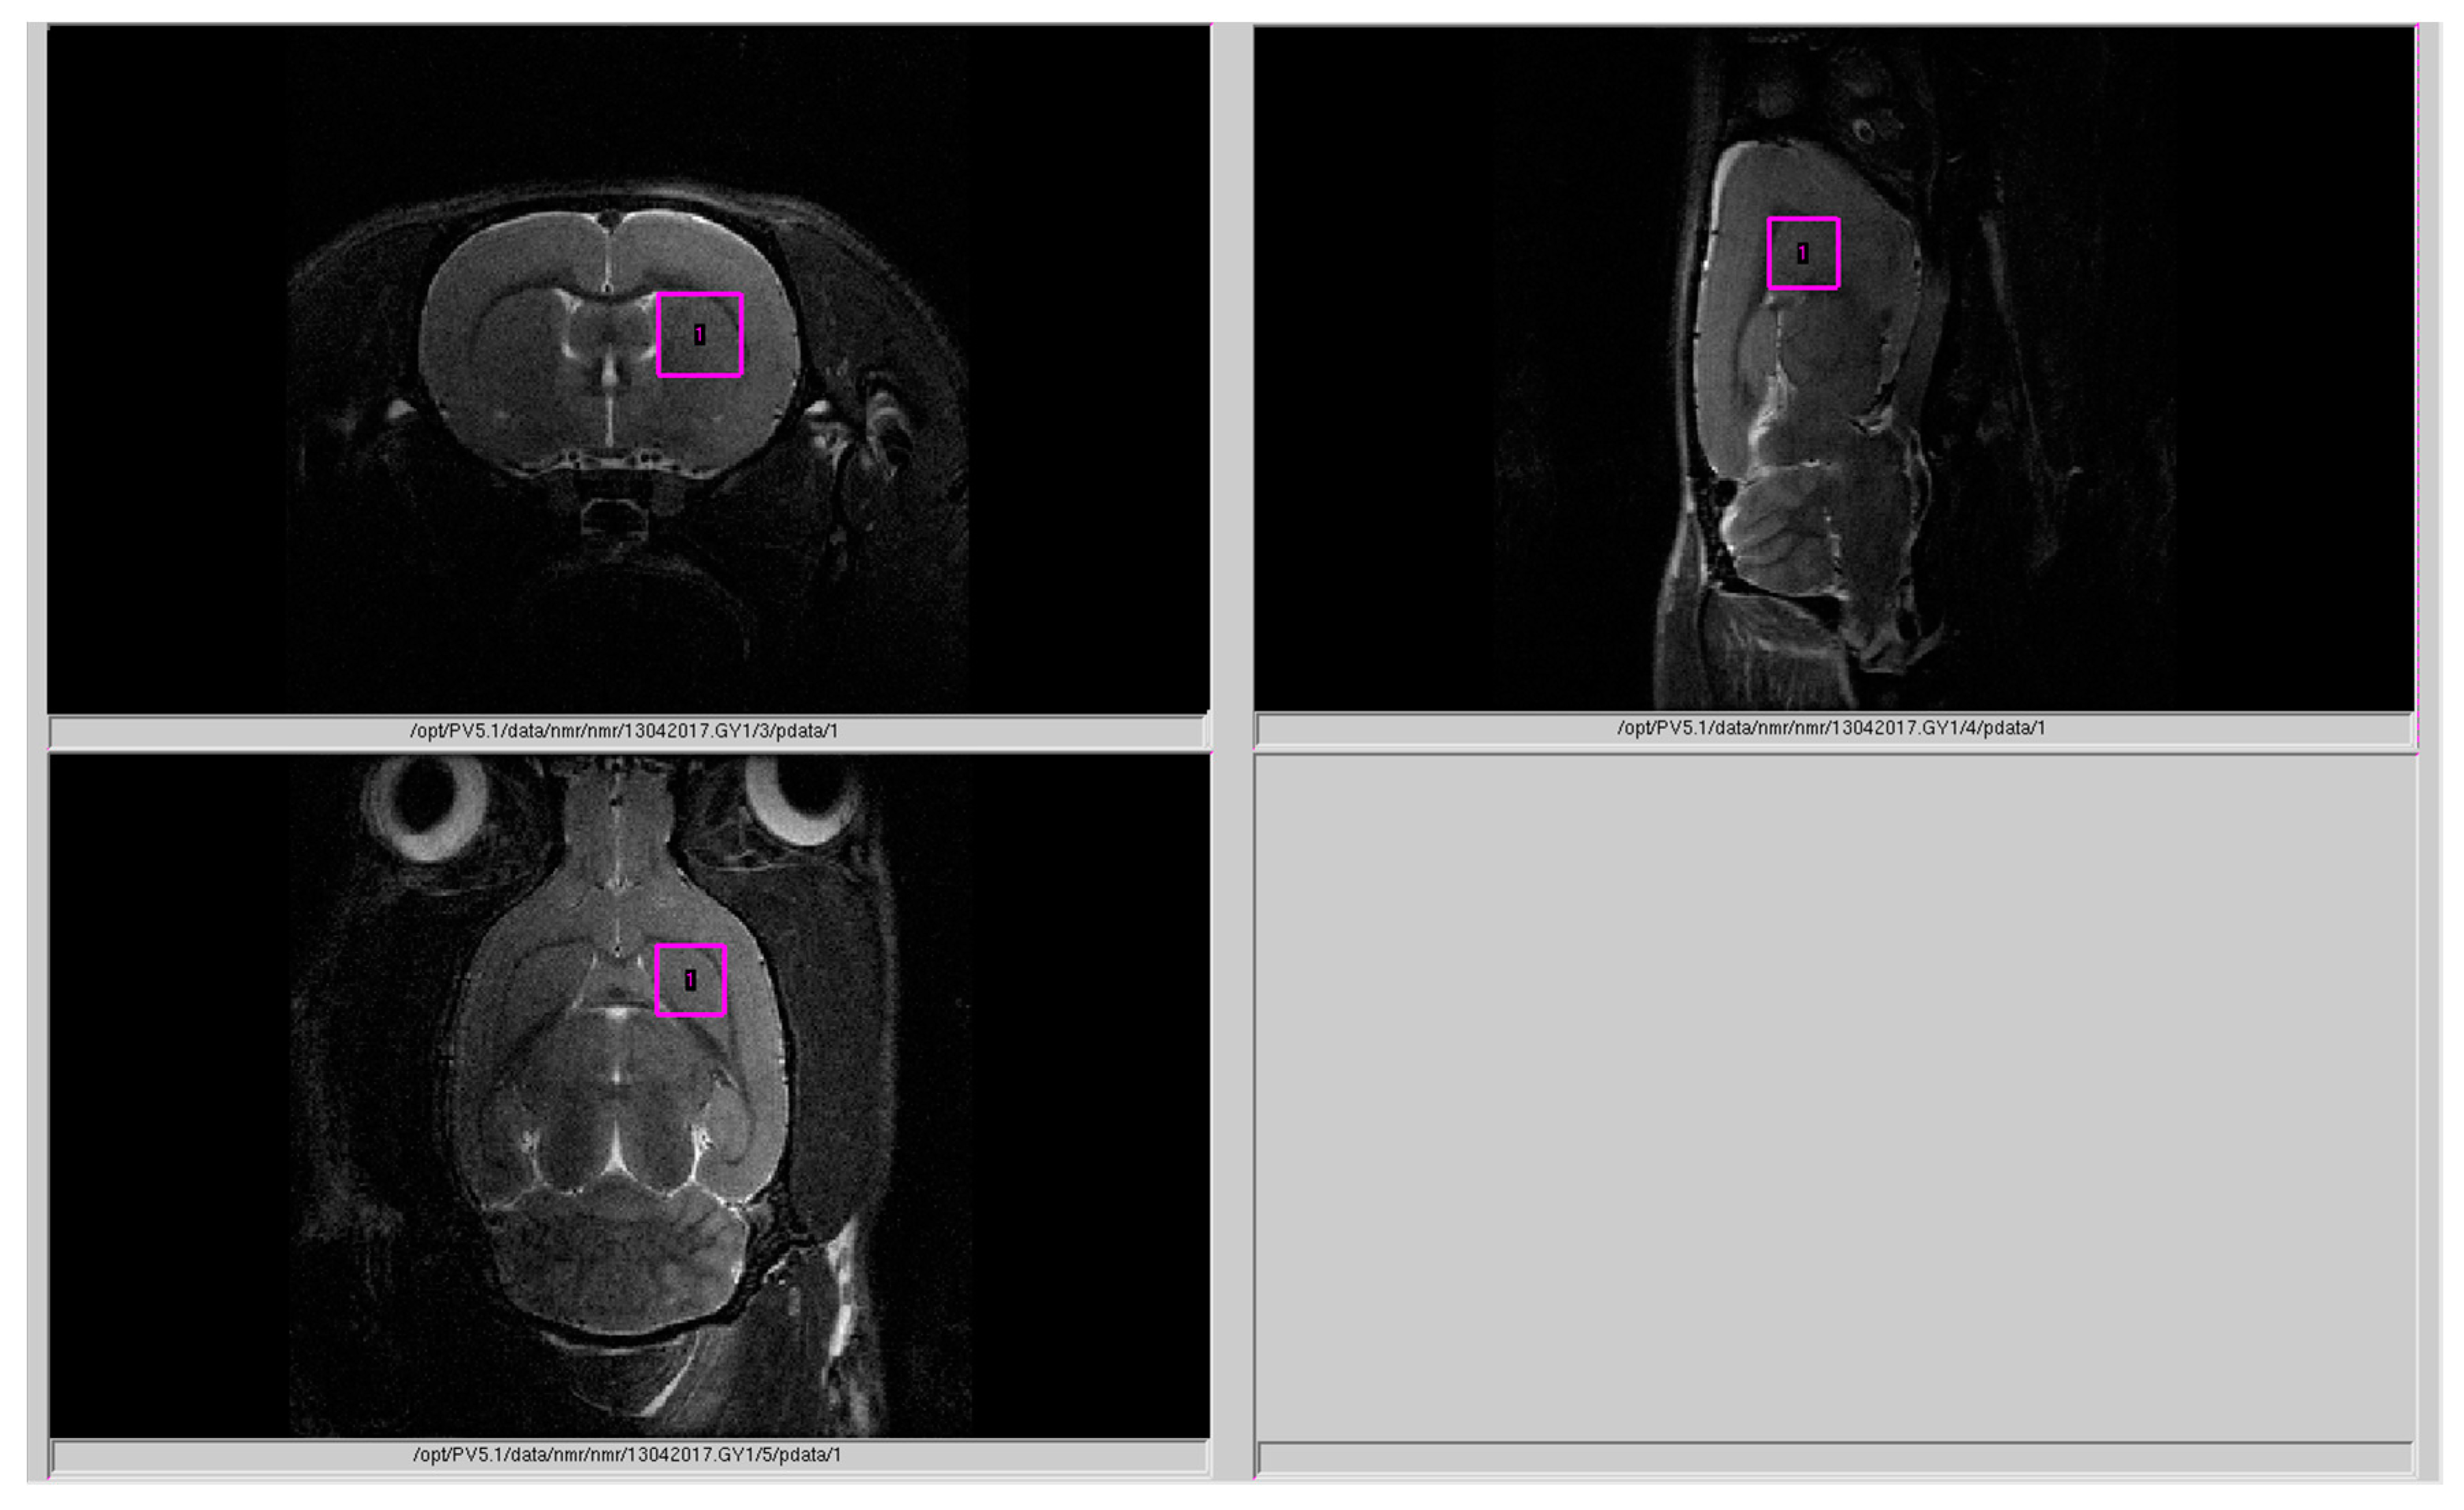

4.3. Magnetic Resonance Spectroscopy (MRS)

4.4. Processing of 1H Spectra

- Tkac, I.; Starcuk, Z.; Choi, I.Y.; Gruetter, R. In vivo 1H NMR spectroscopy of rat brain at 1 ms echo time. Magn. Reson. Med. 1999, 41, 649–656. [Google Scholar] [CrossRef]

- Moshkin, M.P.; Akulov, A.E.; Petrovski, D.V.; Saik, O.V.; Petrovskiy, E.D.; Savelov, A.A.; Koptyug, I.V. Proton magnetic resonance spectroscopy of brain metabolic shifts induced by acute administration of 2-deoxy-d-glucose and lipopolysaccharides. NMR Biomed. 2014, 27, 399–405. [Google Scholar] [CrossRef]